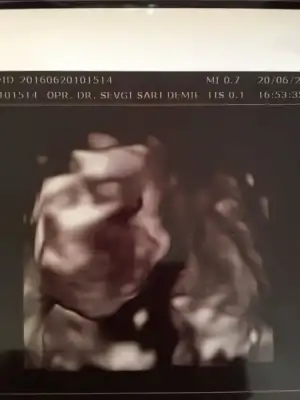

İyi akşamlar kızlar doktora gittik bugün kızım 671 gram 30 cm olmuş :) herşey yolunda dedi doktor çok şükür :) yarında kan ve idrar tahlillerim yapılacak inşallah onlarda temiz çıkar. Kızım ultrason görüntüsünde yine işaret parmağıyla ultrasonda birşeyler anlatmak istiyor gibiydi her doktora gitmemizde işaret parmağıyla mutlaka bi pozu oluyor :)